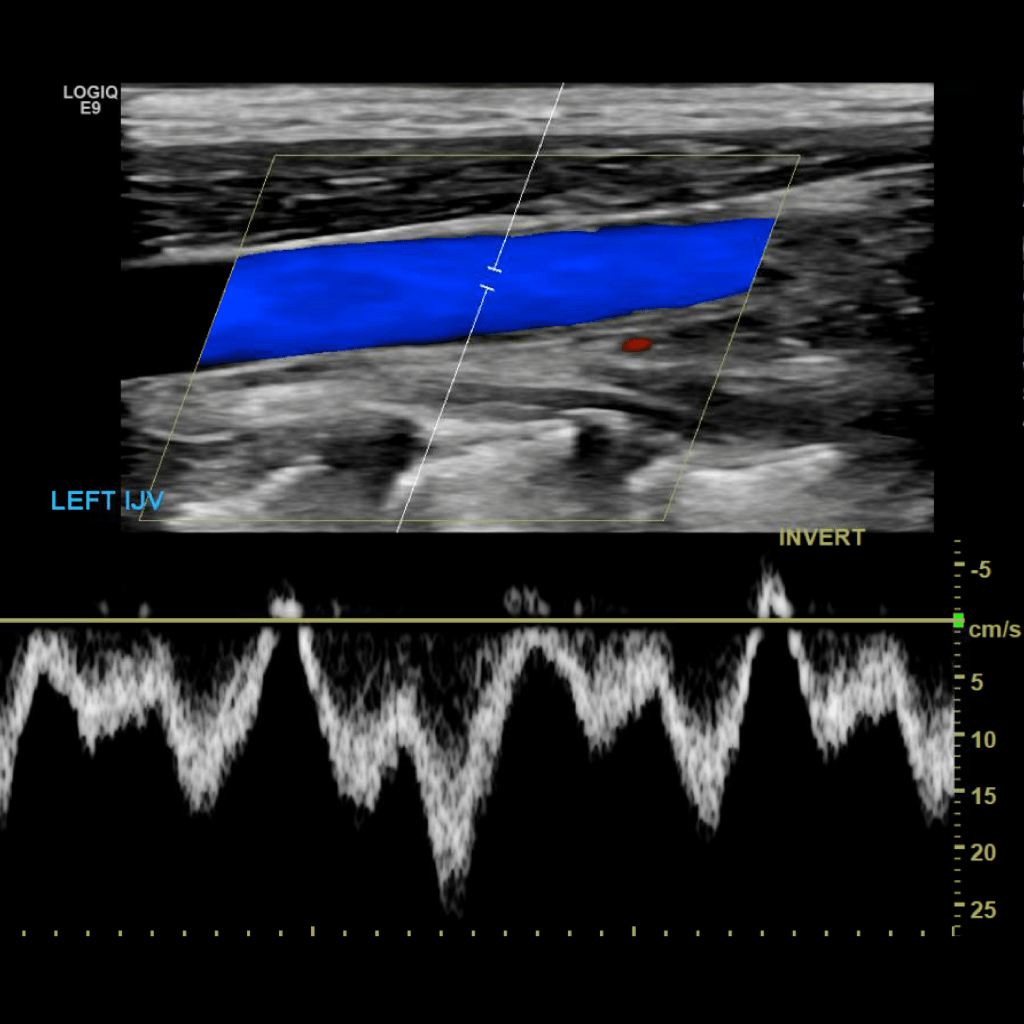

Scan the internal jugular vein in grey scale, compression, color doppler and spectral doppler